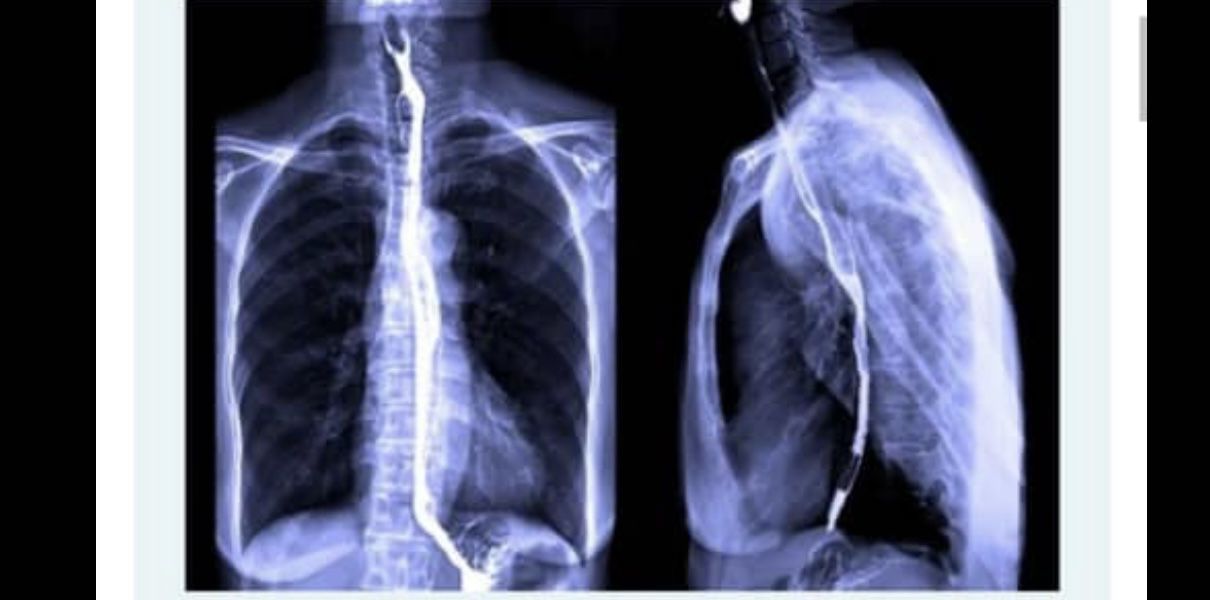

How to improve the SRT used

Gastrointestinal